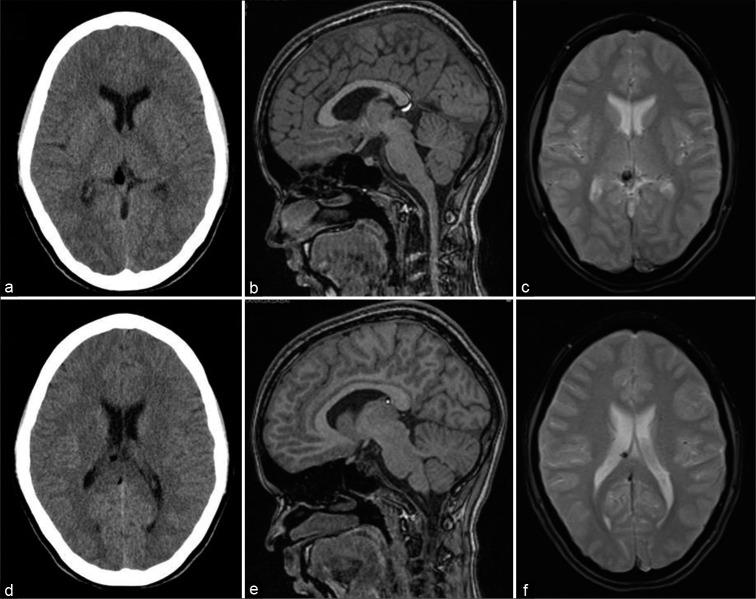

Intracranial lipomas are rare congenital malformations which are present in choroid plexus or subarachnoid locations along the corpus callosum and cisterns. Most of them are identified incidentally during neuroimaging studies done for other indications. Sometimes, they may be associated with other anomalies such as agenesis of corpus callosum and vascular malformations. In magnetic resonance imaging (MRI), they may be associated with chemical shift artifact (CSA) due to their lipid content and can mimic other more serious intracranial lesions. This effect seen in gradient echo MRI sequences can also be used to confirm the presence of these lesions. We report the imaging findings of six patients with intracranial lipomas that showed this chemical shift artifact with a review of the literature.

颅内脂肪瘤是罕见的先天性畸形,存在于脉络丛或沿胼胝体和脑池的蛛网膜下腔位置。它们大多在因其他指征进行的神经影像学检查中偶然发现。有时,它们可能与其他异常有关,如胼胝体发育不全和血管畸形。在磁共振成像(MRI)中,由于其脂质含量,它们可能与化学位移伪影(CSA)相关,并可模仿其他更严重的颅内病变。在梯度回波MRI序列中看到的这种效应也可用于确认这些病变的存在。我们报告了6例显示这种化学位移伪影的颅内脂肪瘤患者的影像学表现,并对文献进行了综述。